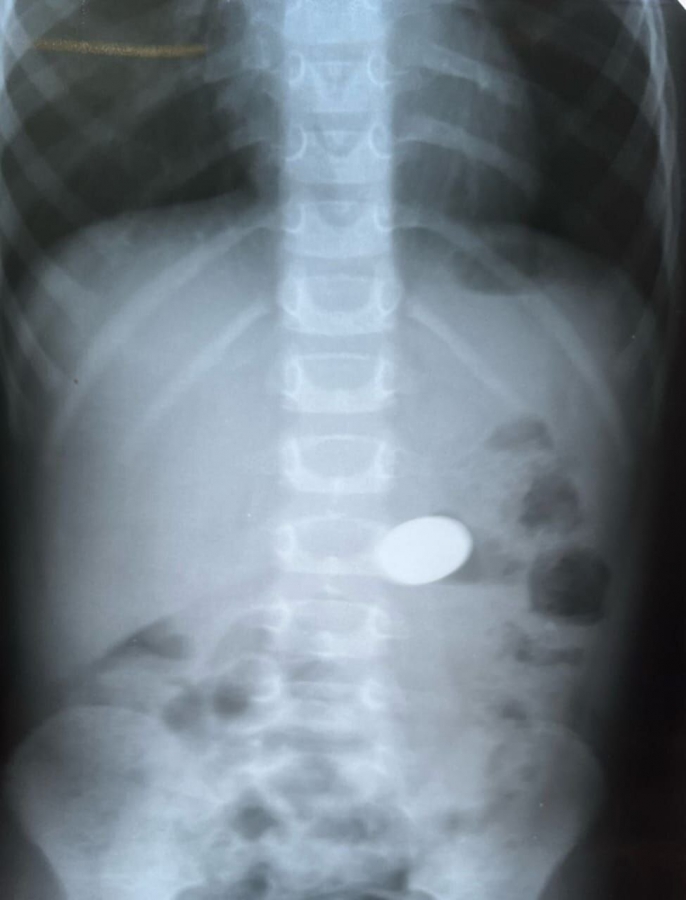

Медики поделились очередной историей про инородные тела в желудках малышей. Недавно один 5-летний ребенок проглотил 10-рублевую монету. Эндоскописты успешно извлекли этот «вклад».